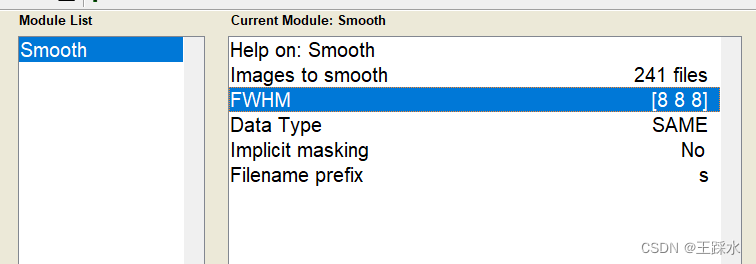

4、空间平滑

两个原因:降低噪音、提高信噪比,在相邻的体素之间做空间平滑,他们的信号噪音程度是随机变化的,平滑后,噪音相互抵消,提高信噪比;平滑后,激活脑区的范围更大,大脑形状不一样,平滑后会让激活脑区重合度更高一些。

FHWM指的是空间平滑kernel大小:高斯分布最高点一半的曲线的宽度,用了默认的8